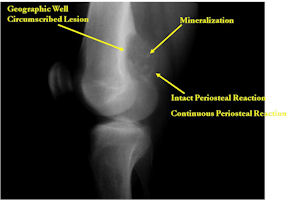

- Geographic, circumscribed lesion usually around 5cm in size.

- There may be expansion of bone, cortical thinning and cortical breakthrough. A soft tissue mass may accompany this lesion but the soft tissue component is usually contained by the periosteum.

- The periosteum remains intact around the soft tissue component. Might need a CT scan to detect the subtle calcification (Egg Shell Rim of Calcification) associated with an intact periosteal reaction

- The lesion may be entirely radiolucent but usually shows some degree of mineralization. Mineralization may appear stippled like cartilage but do not see chondroid pathologically. Mineralization is sometimes better detected on a CT scan rather than an x-ray.

- Usually less surrounding sclerosis than an osteoid osteoma.

- Arise from the Diaphysis (75%) more commonly than Metaphyseal (25%)

- 4 cm to 6 cm in size